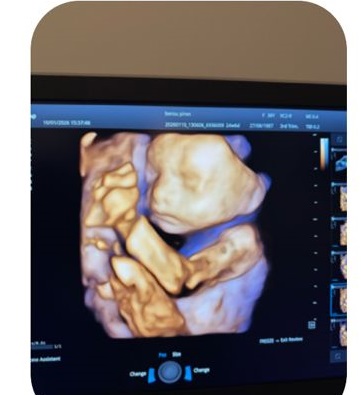

4 boyutlu ultrason, bebeğin üç boyutlu görüntülerinin zaman içinde hareketli olarak izlenmesini sağlayan bir görüntüleme yöntemidir. Bu teknoloji sayesinde bebeğin yüz yapısı, hareketleri ve bazı anatomik özellikleri daha ayrıntılı şekilde incelenebilir.